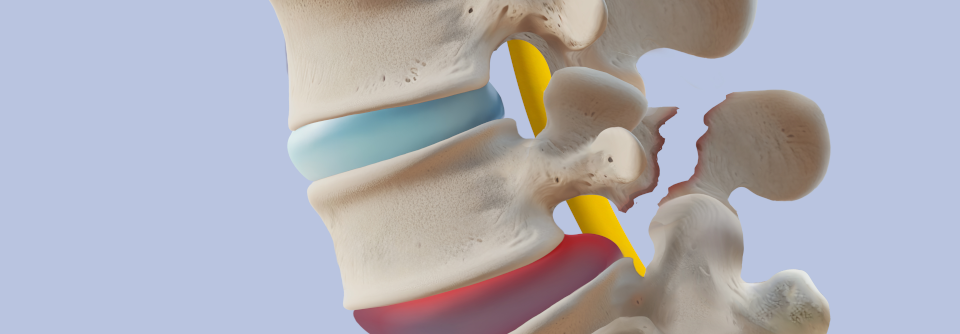

Entwickelt ein Patient mit axialer Spondyloarthritis Antikörper gegen Adalimumab, büßt der TNF-Inhibitor Effektivität ein. Zusätzliches Methotrexat kann das möglicherweise verhindern.

Die therapierefraktäre axiale Spondyloarthritis wird u.a. mit Adalimumab behandelt. Ein Viertel der Patienten setzt den TNF-Antikörper jedoch im ersten Jahr wieder ab – meist wegen mangelnder Effektivität. Ursache dafür können Antikörper sein, die die Pharmakokinetik von Adalimumab und damit seine Wirksamkeit beeinträchtigen. Etwa 30 % der Patienten weisen nach 24 Wochen die Antikörper auf, was mit geringen bis nicht nachweisbaren Konzentrationen des Biologikums einhergeht.